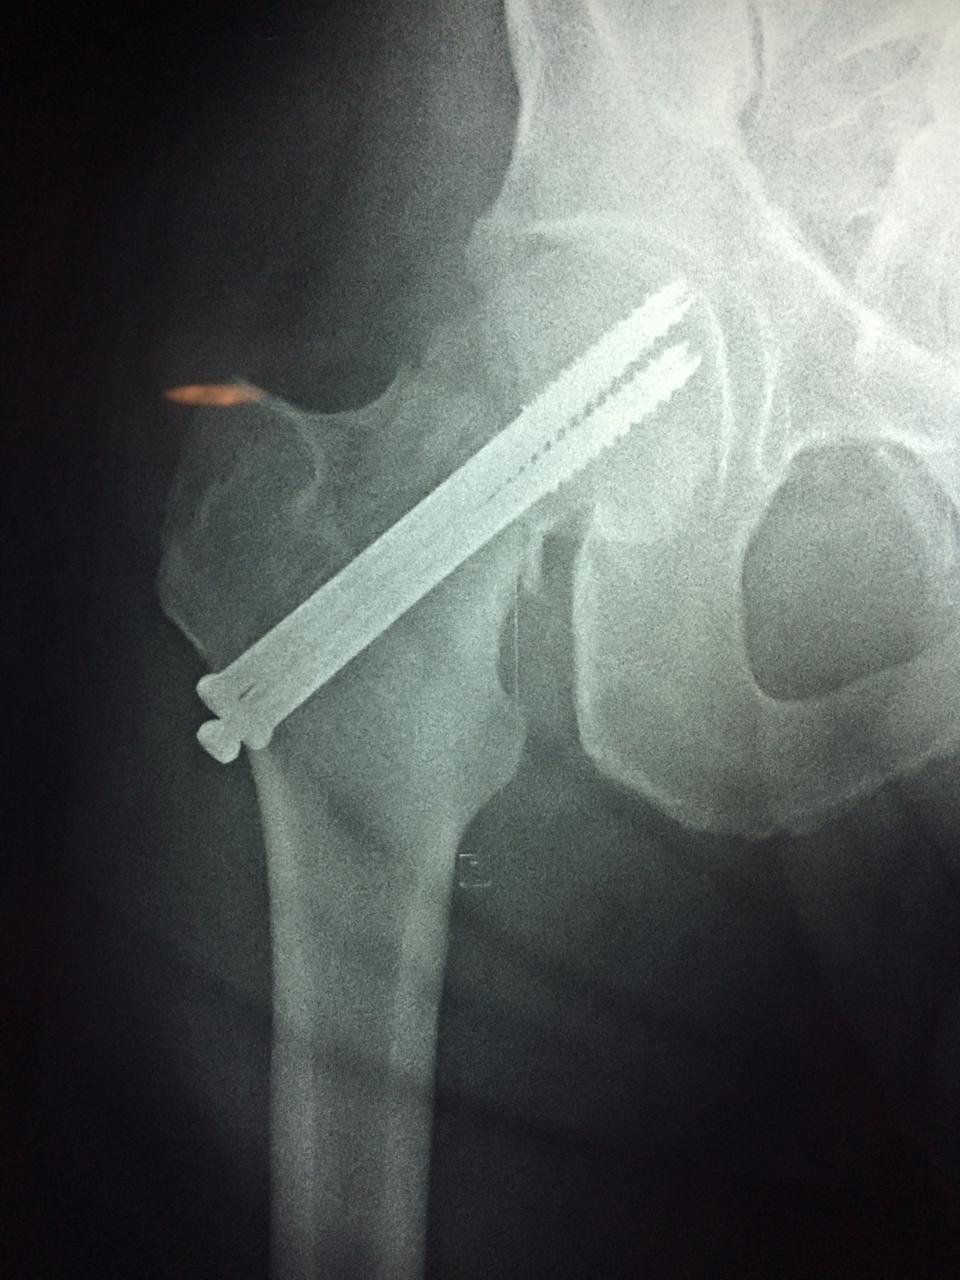

La cirugía de fractura de cadera se realiza para reparar una ruptura en la parte superior del hueso del muslo. Este hueso se denomina fémur.

Es parte de la articulación coxofemoral. Si una fractura de cadera no recibe tratamiento, es posible que deba permanecer en una silla o en la cama.

A menudo se recomienda la cirugía para reparar la fractura debido a dichos riesgos.